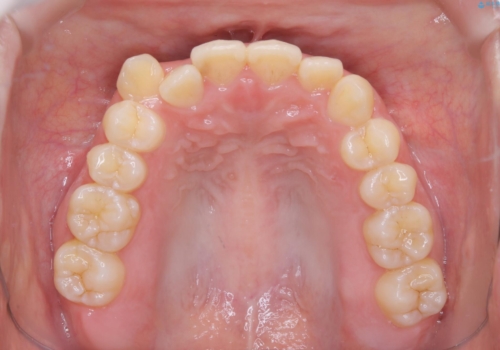

八重歯とクロスバイト:インビザライン治療

- 八重歯が気になるとの事でご相談にいらした方です。

インビザラインで綺麗に並べました。

気になっていた八重歯が綺麗になって大変喜んでいただけました。